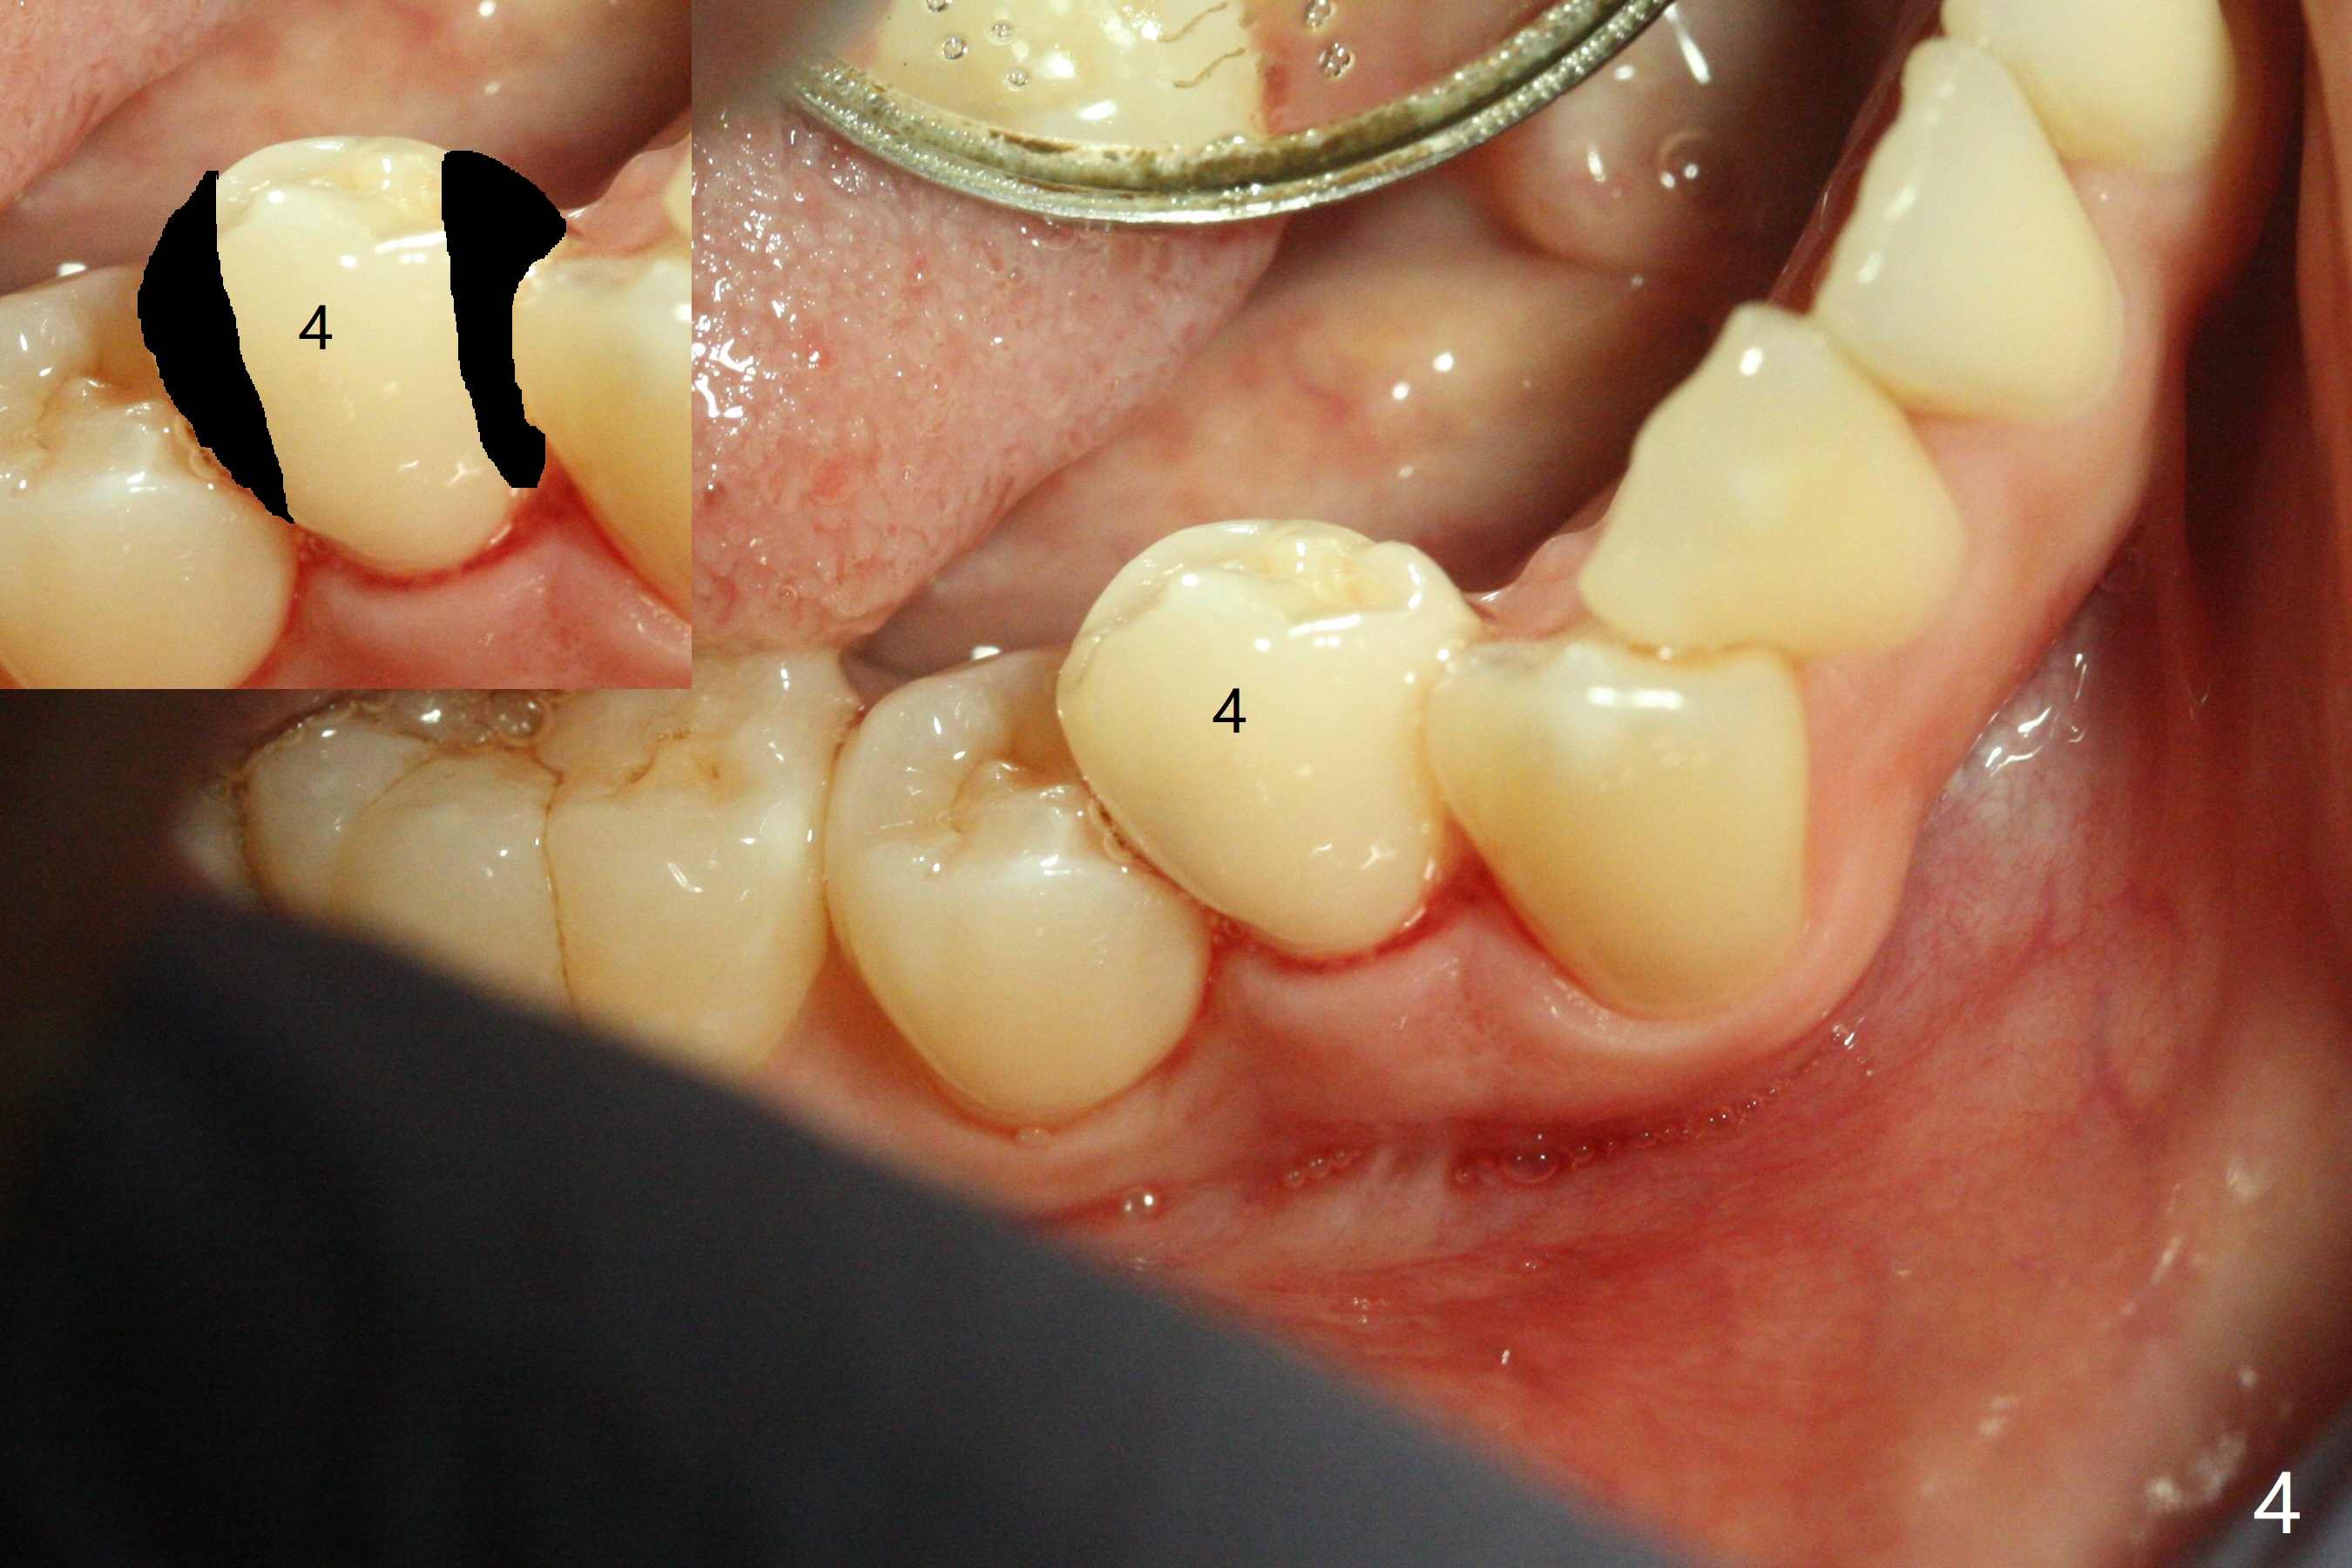

A 34-year-old woman with crowding particularly at LR 4/5 (Fig.1) and suspected DO caries of LR4 (Fig.2) returns with symptom of pulpitis and "cavity" at LR5 (MO). New Bitewing confirms LR4 DO caries (Fig.3). Treatment plan is to extract LR4 and place composite at LR5 if present. Extraction turns out to be difficult because of nervousness and TMD of the patient and crowding. The proximal areas of LR4 requires removal before luxation without traumatizing the neighboring teeth (Fig.4 insert black areas). In fact there is no caries at LR5. When the patient returns for orthodontic treatment, bracketing at LR5 should consider overcorrection (Fig.5 (black rectangle vs. red line: height of contour)) due to the tilted long axis (Fig.1).